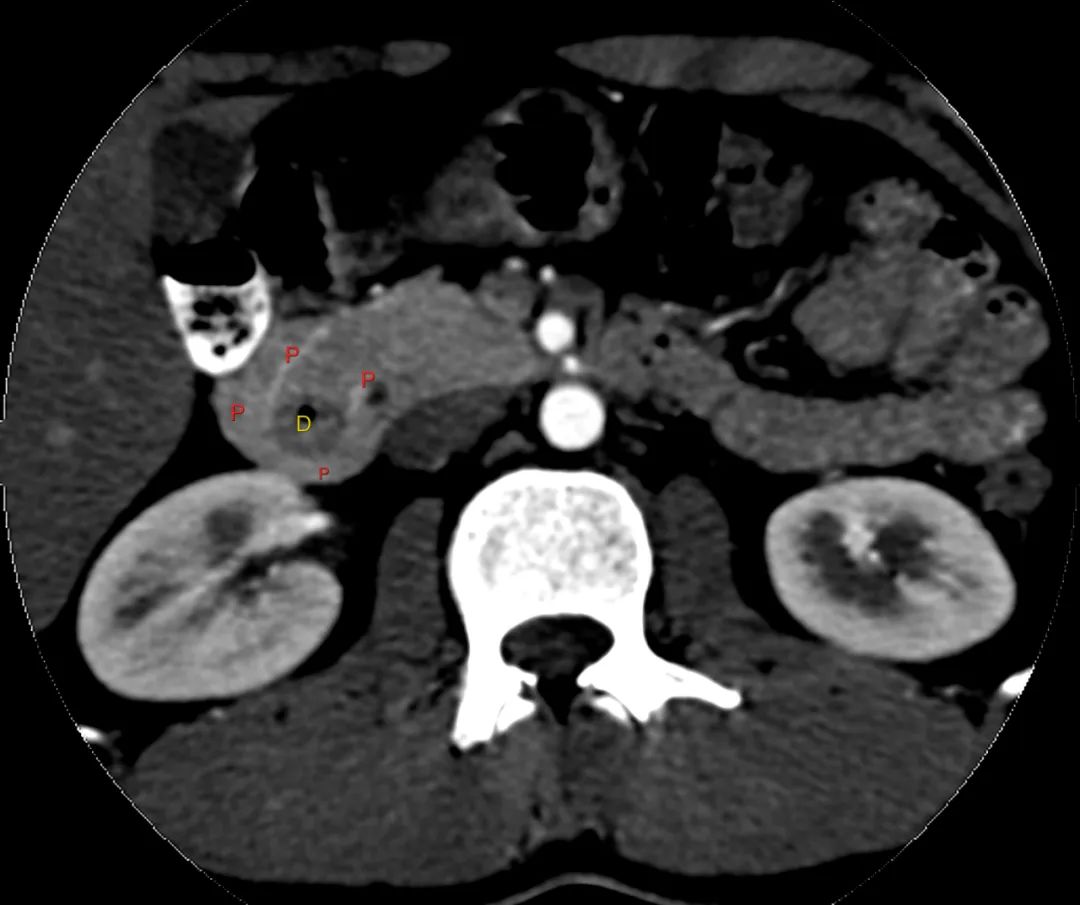

带注释的动脉期图像显示增强胰腺实质(标记为P)完全包裹十二指肠(标记为D)。

环状胰腺是由腹芽不旋转导致十二指肠被胰腺不同程度包裹的结果。完全性环状胰腺出现在新生儿有梗阻,并可偶然发现在成人,胰腺炎可能是成人的一种表现特征。